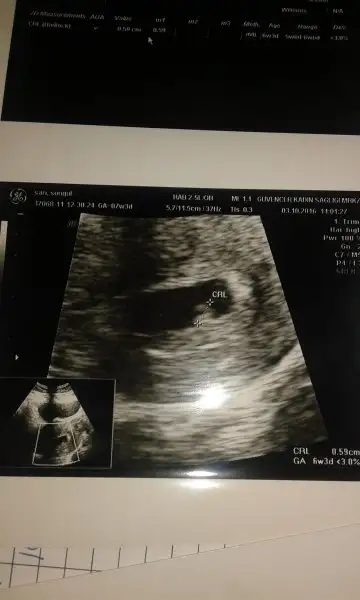

Hazirandaki gebeliğim sonlandı maalesef.pıhtılaşma olmuş ve bebeğimin kalbi durmuş.şimdi allahın izniyle tekrar hamileyim kan suşandırıcı iğne kullanıyyorum.yorum yaparmısınız usg lere.2 side karından .ilk resim 7 hafta 2.si 6+3.

Kac haftalikti bu foto.? 13. Haftada soyluyorlar cinsiyeti. Hade inşallah kizina bi erkek kardeş gelir ... Rabbim kiz nasip etmis inşallah oglanida nasip eder . Zira her iki nimette tarifsiz :)

Canim kizinin varsa böyle ilk ultrason fotolari yükle ozaman daha net ortaya cikiyo cünkü her kadin genelleme kizi bi tarafta erkegi bi tarafta tasiyo sag sol o kadina göre deisiyp bendede tutmadi teori :)